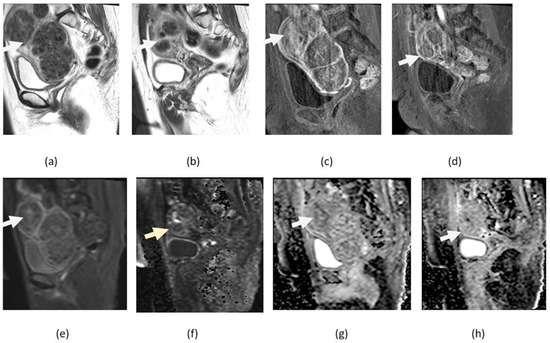

4.2. Endometrial Cancer

4.3. Ovarian Cancer

5. Pitfalls of DWI

5.1. T2 Shine-Through Effect

5.2. T2 Blackout Effect